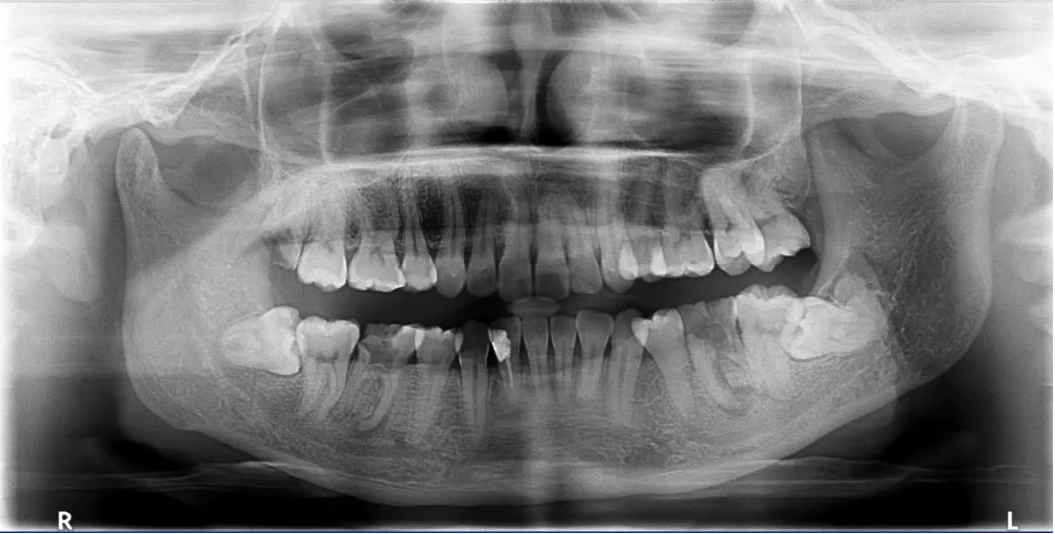

【病例5】

71岁,女性,右下颌后牙缺失要求种牙

曲断片:全面了解患者口腔情况

种植:缺牙位置、上颌窦、下颌神经管

牙周:牙槽骨、牙结石

牙体:龋坏、根尖炎、楔缺、合面磨耗

上颌前牙区阴影:舌头位置不对→重拍?

下颌神经管显示不清:影响种植设计→进一步检查?

初步诊断及预判:结合临床检查,哪些重点检查;影像经验,14、15,12、21,23,11、22

下颌种植主要判断:神经管走行及位置

左侧神经管下壁显示清晰,但上壁右侧神经管不清晰,前段疑似膨大。